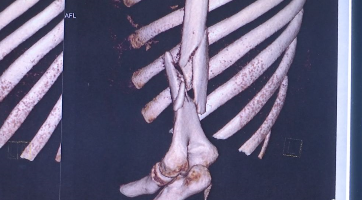

“拍了片子以后大家都大吃一惊,整个肱骨粉碎性骨折!”武进人民医院骨科主任历晓龙介绍。

通过X片可以看出,许同学骨折极其明显,骨头断为两截。

医生介绍,人体上臂的肱骨承受牵引力的能力较强,比如平时拎东西时就是一种向下的牵引力;而掰手腕时是一种剪切力,肱骨承受剪切力的能力很弱。如果使力的方向或姿势不对,特别是在双方势均力敌时突然发力,就容易造成肱骨螺旋形骨折。